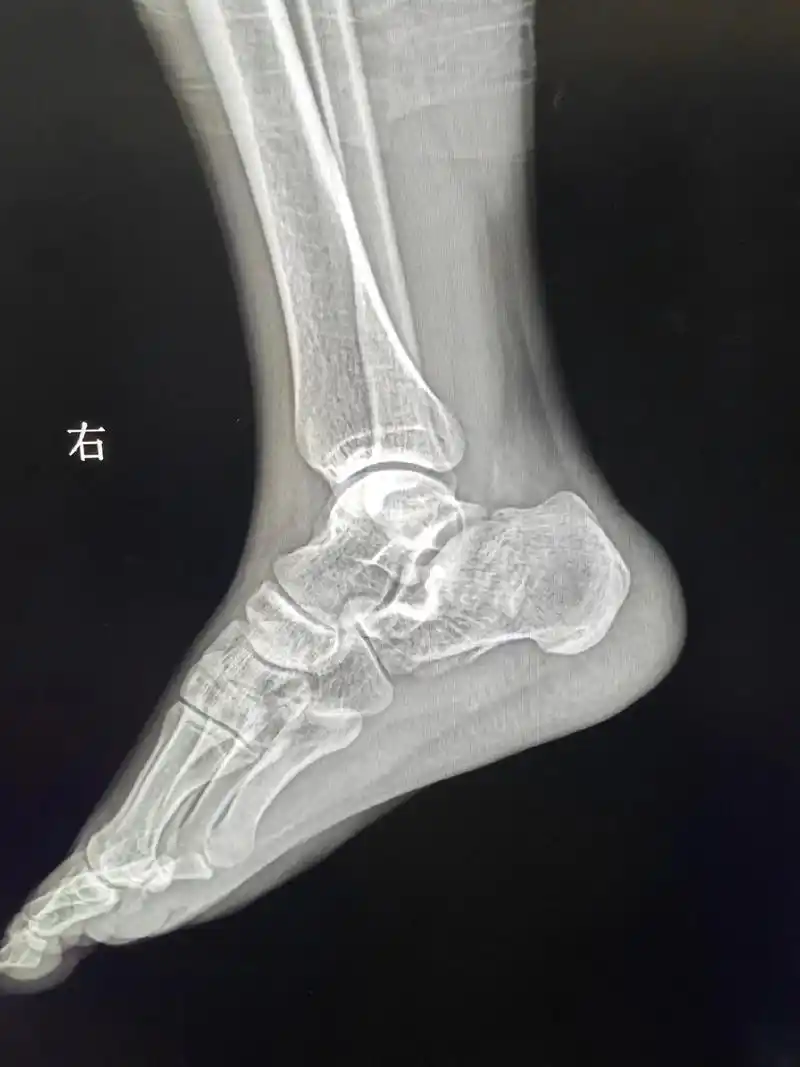

高处坠落脚跟着地—右跟骨粉碎性骨zhe#医学影像 - 抖音

跟骨骨折后脚跟的x光片